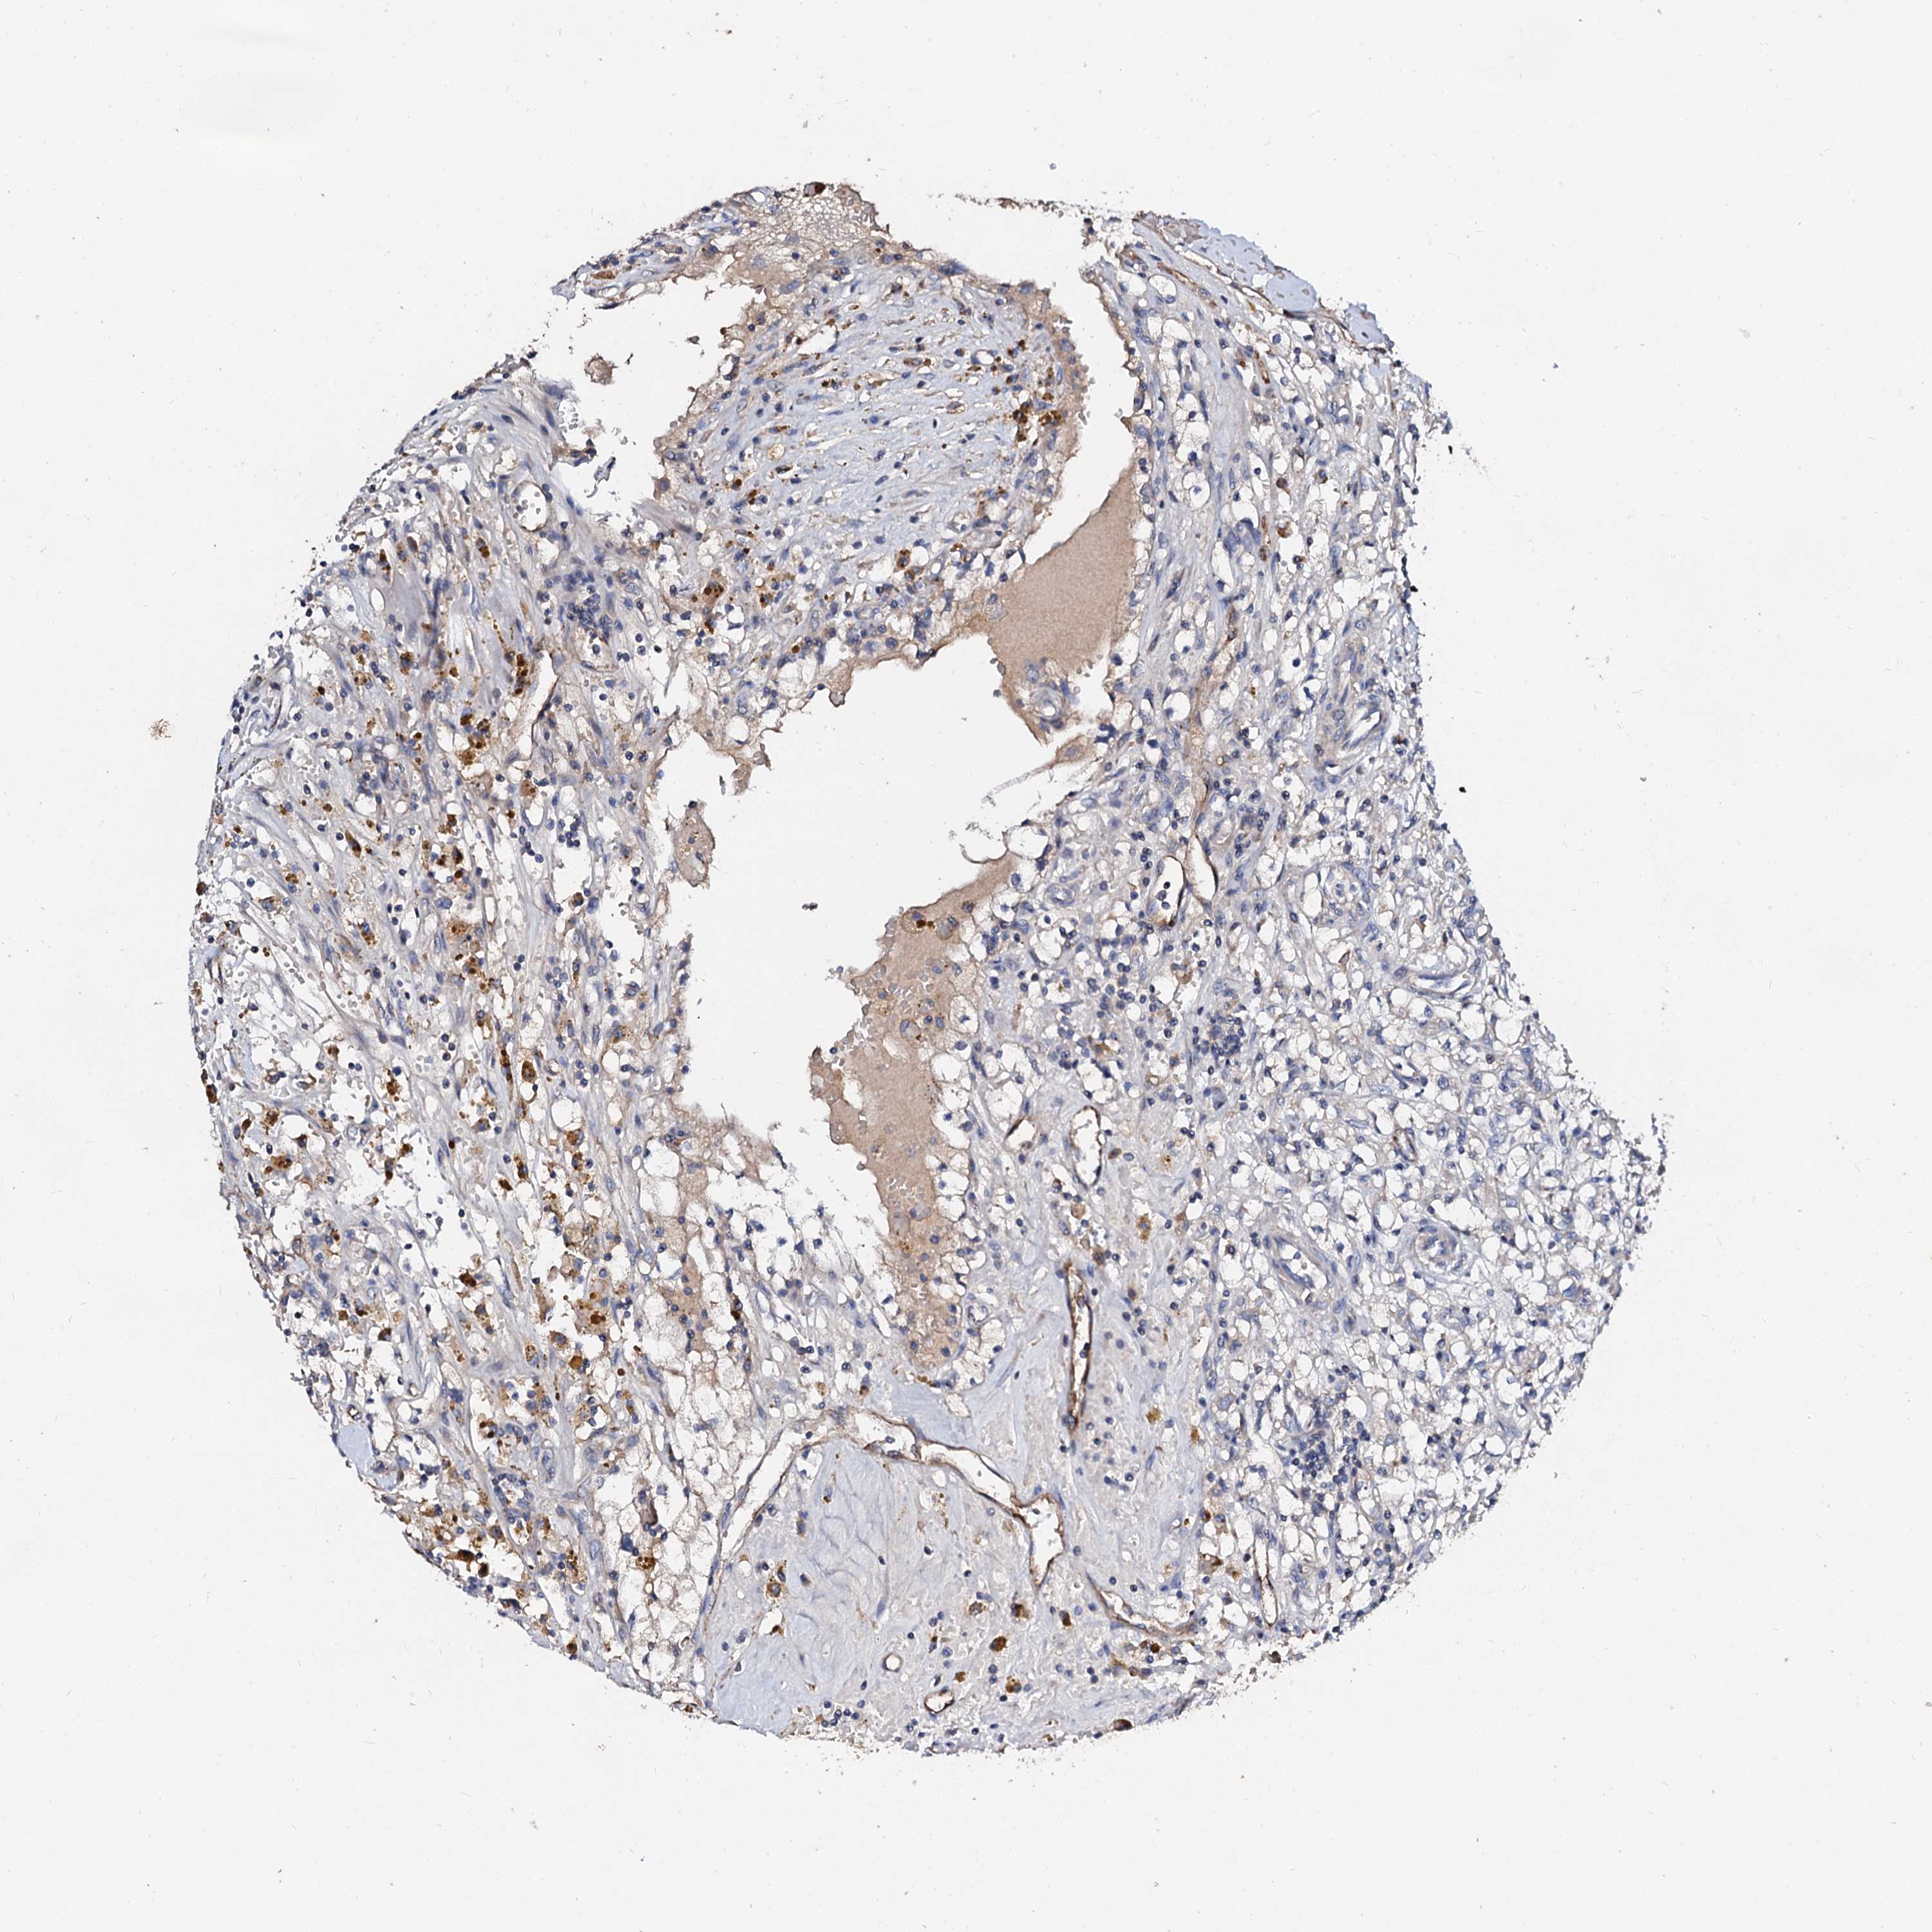

KIDNEY RENAL CLEAR CELL CARCINOMA (VALIDATION) - Interactive survival scatter ploti

The Survival Scatter plot shows the clinical status (i.e. dead or alive) for all individuals in the patient cohort, based on the same data that underlies the corresponding Kaplan-Meier plots. Patients that are alive at last time for follow-up are shown in blue and patients who have died during the study are shown in red.

The x-axis shows the expression levels (FPKM) of the investigated gene in the tumor tissue at the time of diagnosis. The y-axis shows the follow-up time after diagnosis (years). Both axes are complimented with kernel density curves demonstrating the data density over the axes. The top density plot shows the expression levels (FPKM) distribution among dead (red) and alive patients (blue). The right density plot shows the data density of the survived years of dead patients with high and low expression levels respectively, stratified using the cutoff indicated by the vertical dashed line through the Survival Scatter plot. This cutoff is automatically defined based on the FPKM cutoff that minimizes the p-score. The cutoff can be changed by dragging the vertical line or by entering a cutoff value in the square labeled "Current cut-off".

Under the Survival Scatter plot the p-score landscape (black curve; left axis) is shown together with dead median separation (red curve; right axis). Dead median separation is the difference in median mRNA expression between patients who have died with high and low expression, respectively. It is calculated as follows: median FPKM expression of dead patients with high expression - median FPKM expression of dead patients with low expression. This is intended to aid the user in visually exploring custom cutoffs and the associated p-scores and dead median separation.

Individual patient data is displayed and can be filtered by clicking on one or more of the category buttons on the top of the page. Categories describing expression level and patient information include: high, low, alive, dead, female, male and tumor stages. The scale of the x-axis can be toggled between linear and log-scale by clicking on the "x log" button. Mouse-over function shows TCGA ID, patient information and mRNA expression (FPKM) for each patient.

& Survival analysisi

Kaplan-Meier plots summarize results from analysis of correlation between mRNA expression level and patient survival. Patients were divided based on level of expression into one of the two groups "low" (under cut off) or "high" (over cut off). X-axis shows time for survival (years) and y-axis shows the probability of survival, where 1.0 corresponds to 100 percent.

FIBIN is not prognostic in Kidney Renal Clear Cell Carcinoma (validation)

Best expression cut offi

Based on the FPKM value of each gene, patients were classified into two groups and association between prognosis (survival) and gene expression (FPKM) was examined. The best expression cut-off refers the FPKM value that yields maximal difference with regard to survival between the two groups at the lowest log-rank P-value. Best expression cut-off was selected based on survival analysis .

When clicking on this number, the vertical dashed line indicating cut-off, the interactive survival plot, and the Kaplan-Meier curve will be adjusted to show results based on the best expression cut-off.

: 2.81

P scorei

Log-rank P value for Kaplan-Meier plot showing results from analysis of correlation between mRNA expression level and patient survival.

N/A

TCGA RNA samplesi

RNA-seq data is reported as average FPKM (number Fragments Per Kilobase of exon per Million reads), generated by the The Cancer Genome Atlas (TCGA) .

Normal distribution across the dataset is visualized with box plots, shown as median and 25th and 75th percentiles. Points are displayed as outliers if they are above or below 1.5 times the interquartile range. FPKM values of the individual samples are presented next to the box plot.

Average pTPM 9.9

Number of samples 100